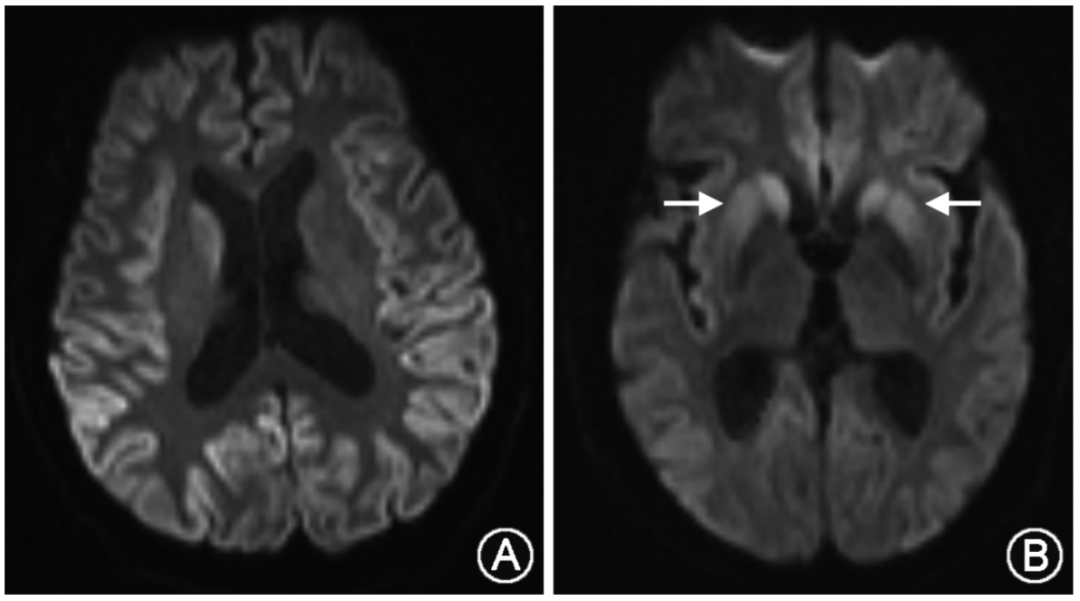

neurol:八成克雅病患者首次就诊被误诊

图片尺寸1000x611